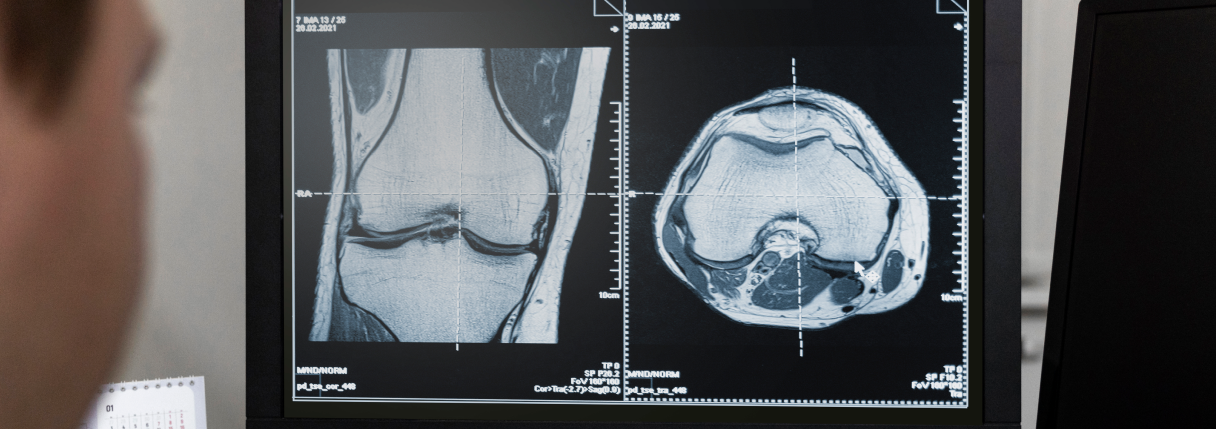

A tomografia do joelho é um exame de imagem que utiliza raios X e tecnologia computadorizada para gerar cortes transversais detalhados da articulação. É especialmente útil para avaliar estruturas ósseas, identificar fraturas, analisar desalinhamentos e investigar alterações articulares que podem provocar dor, inchaço ou limitação de movimento.

A tomografia é excelente para avaliar ossos e fraturas, mas tem limitações para analisar tecidos moles como ligamentos e meniscos. Esses elementos são melhor visualizados pela ressonância magnética.

No entanto, a tomografia pode identificar sinais indiretos de lesões ligamentares, luxações, avulsões ósseas e alterações associadas a traumas.